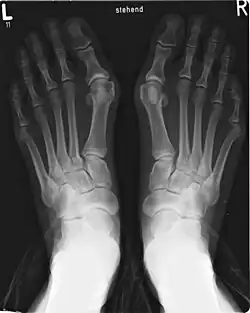

Vbočený palec (lat. hallux valgus) je získaná deformita nohy. Jde o komplexní postižení přednoží s poruchou postavení palce.

Nesprávné postavení palce přetěžuje ostatní části nohy. Kvůli vbočenému palci mohou vznikat různé typy bolesti přednoží, stav může komplikovat bursitida nebo artritida.

Nejčastěji jsou vrozené – patří k nim nesprávný poměr délek nártních kostí, nevhodný sklon kloubních ploch a snížená pevnost vazů a svalů. Podílejí se na nich také nemoci, které vedou ke změnám na měkkých tkáních a kostech, např. revmatoidní artritida, parézy nebo degenerativní onemocnění nervové tkáně.